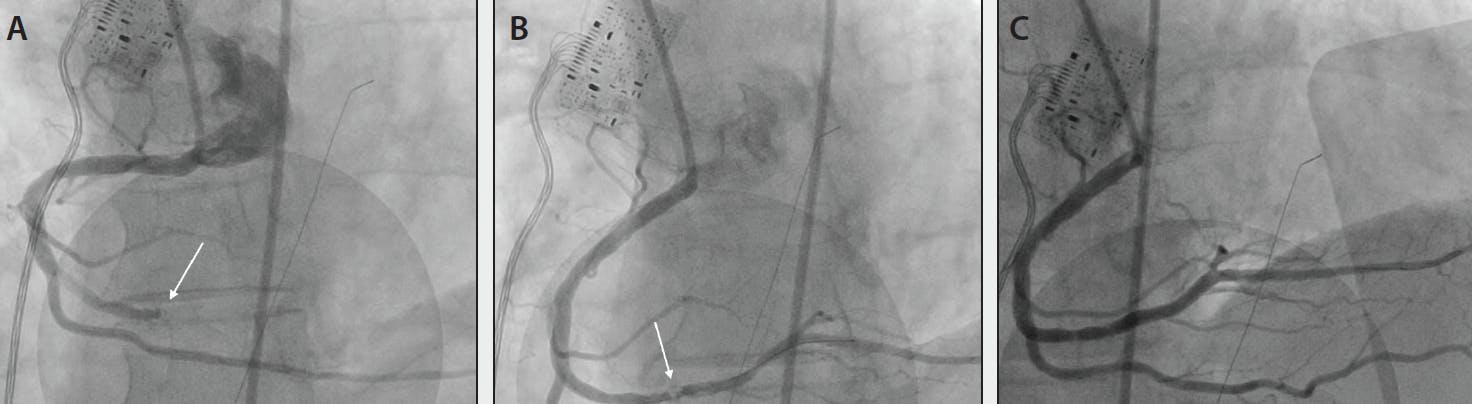

THROMBOTIC OCCLUSION IN DISTAL RCA

Figure 5. Coronary angiography demonstrated a thrombotic occlusion of the distal RCA (white arrow) (A). CAT RX was used frontline, and there was clear identification of the underlying lesion (B). Following balloon and stent, TIMI 3 flow was achieved through the RCA, with myocardial perfusion normalization (C).

Below, we highlight a case in which continuous power aspiration with CAT RX was used successfully and achieved positive results.